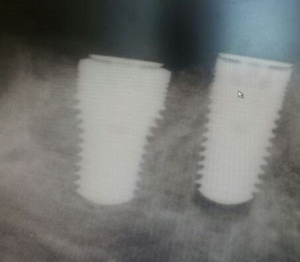

Удаление+ имплантация.

Фронт. Удаление + Конмет(Россия).

Бок. отдел. Удаление+Implant Direct (USA).

Левый крайний диаметр 7.0 мм,для использования одномоментно в лунку моляра.